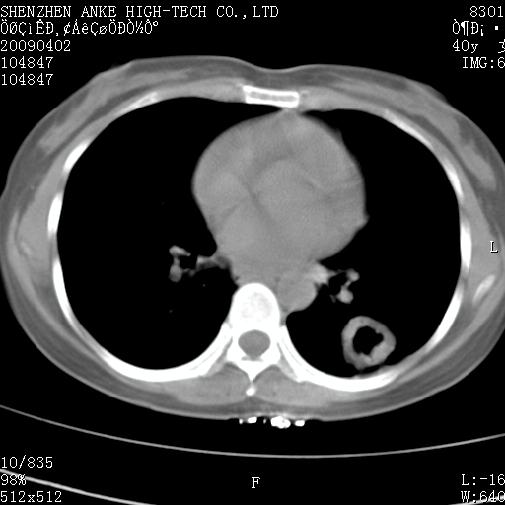

以下是引用随光逐影在2009-4-2 12:16:00的发言:[br]考虑左肺下叶背段继发性肺结核,结核球形成;建议追踪复查。

以下是引用gudu医生在2009-4-2 11:27:00的发言:[br]周围型肺癌

以下是引用卜一在2009-4-2 13:31:00的发言:[br][br] [br] 空洞壁厚不均 胸膜凹陷征。周围型肺癌可能 不排除干酪坏死型肺结核及坏死性肉芽肿。 [br] [br]支持!

以下是引用ct诊断高手在2009-4-2 13:04:00的发言:[br]空洞壁厚不均 胸膜凹陷征。周围型肺癌可能 不排除干酪坏死型肺结核及坏死性肉芽肿。